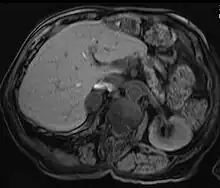

Liver

Hepatic adenomas are a rare benign tumour of the liver, which may present with hepatomegaly or other symptoms.